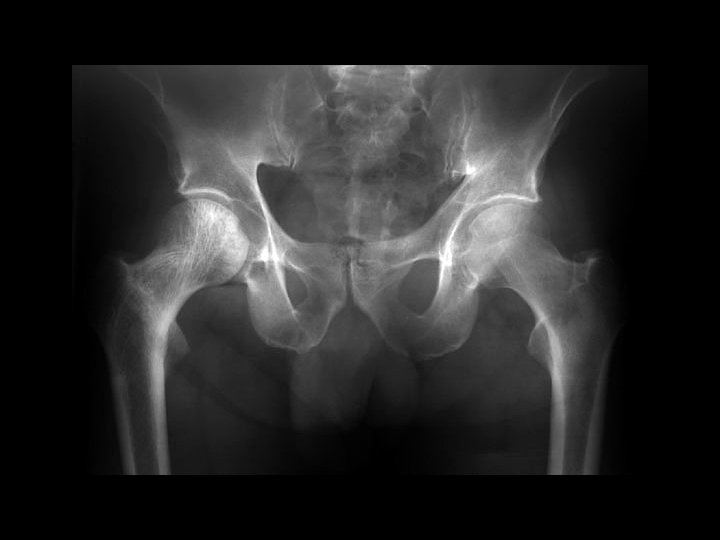

Ankylosing Spondylitis • • Findings: – fused SI joints – right hip erosions – lumbar syndesmophytes Sero-negative chronic inflammatory disease Starts in the low back and progesses upward ddx (sacroilitis) – bilateral • ank spond • IBD – Unilateral • Reiter’s • psoriasis